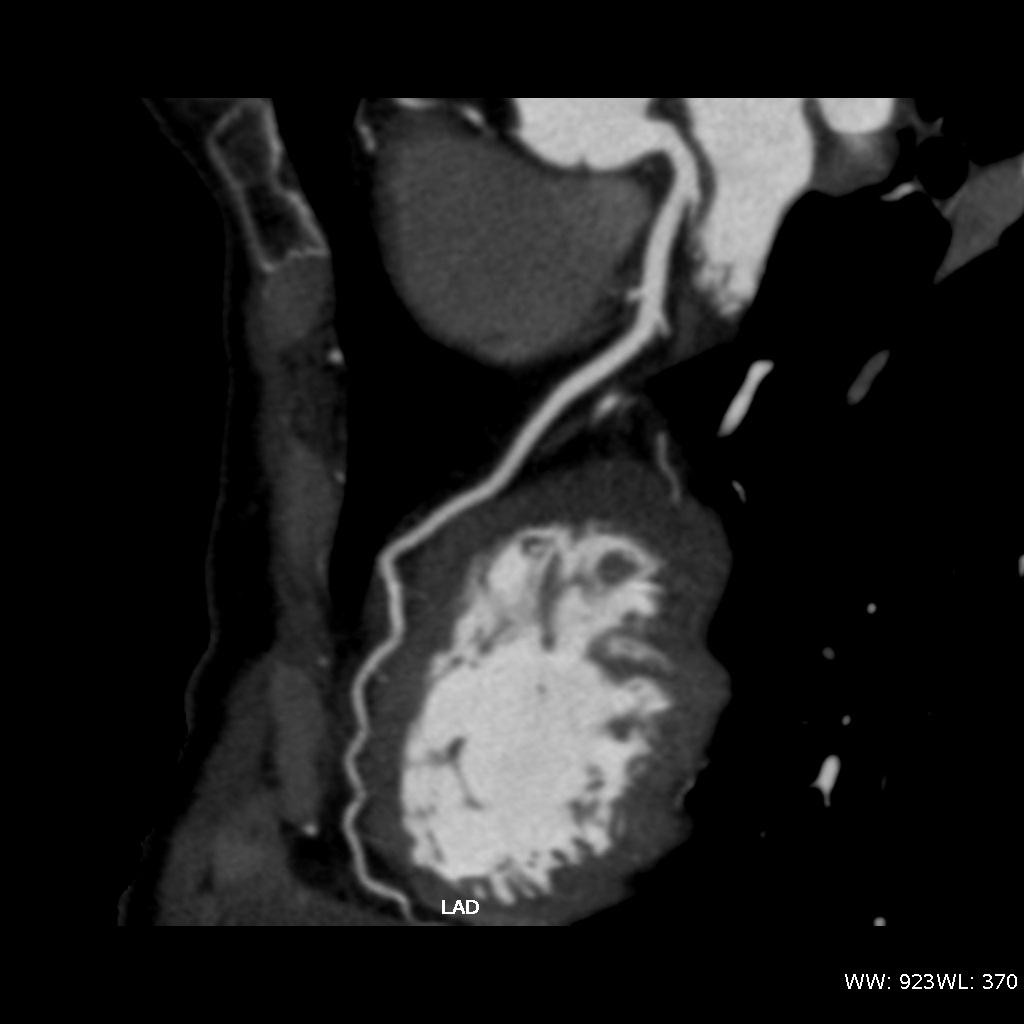

Fig. 3., 4., 5.: CT coronarography: Normal anatomy, volume rendered image and curved reformatted image Plaque causing stenosis on LAD coronary artery